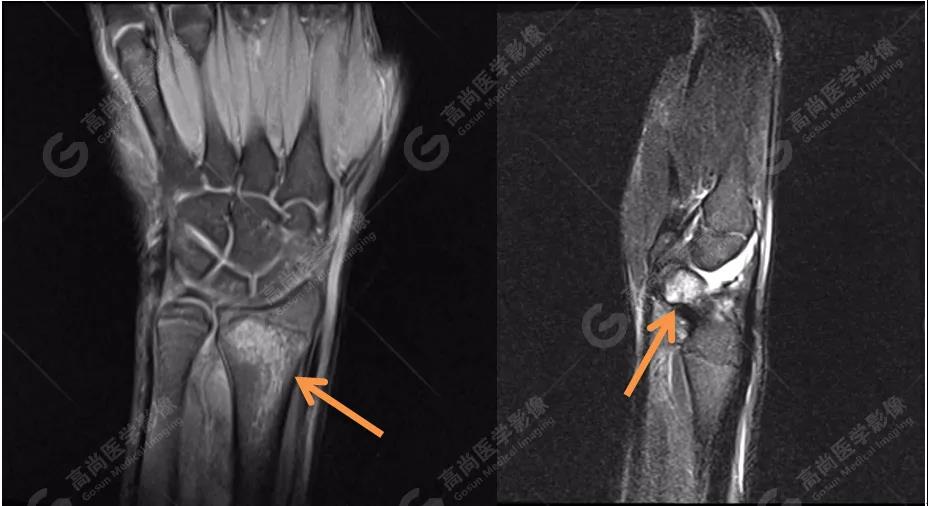

4、MRI圖像

MRI被認為是顯示骨髓水腫最好的方法。本著嚴謹、負責的態(tài)度,我們?yōu)椴』济赓M行MRI檢查,進一步確認診斷。

MR質子壓脂序列圖像進一步證實:左側橈骨遠端與右側舟狀骨骨髓水腫!范圍也與雙能CT骨髓成像圖有很好的吻合度。